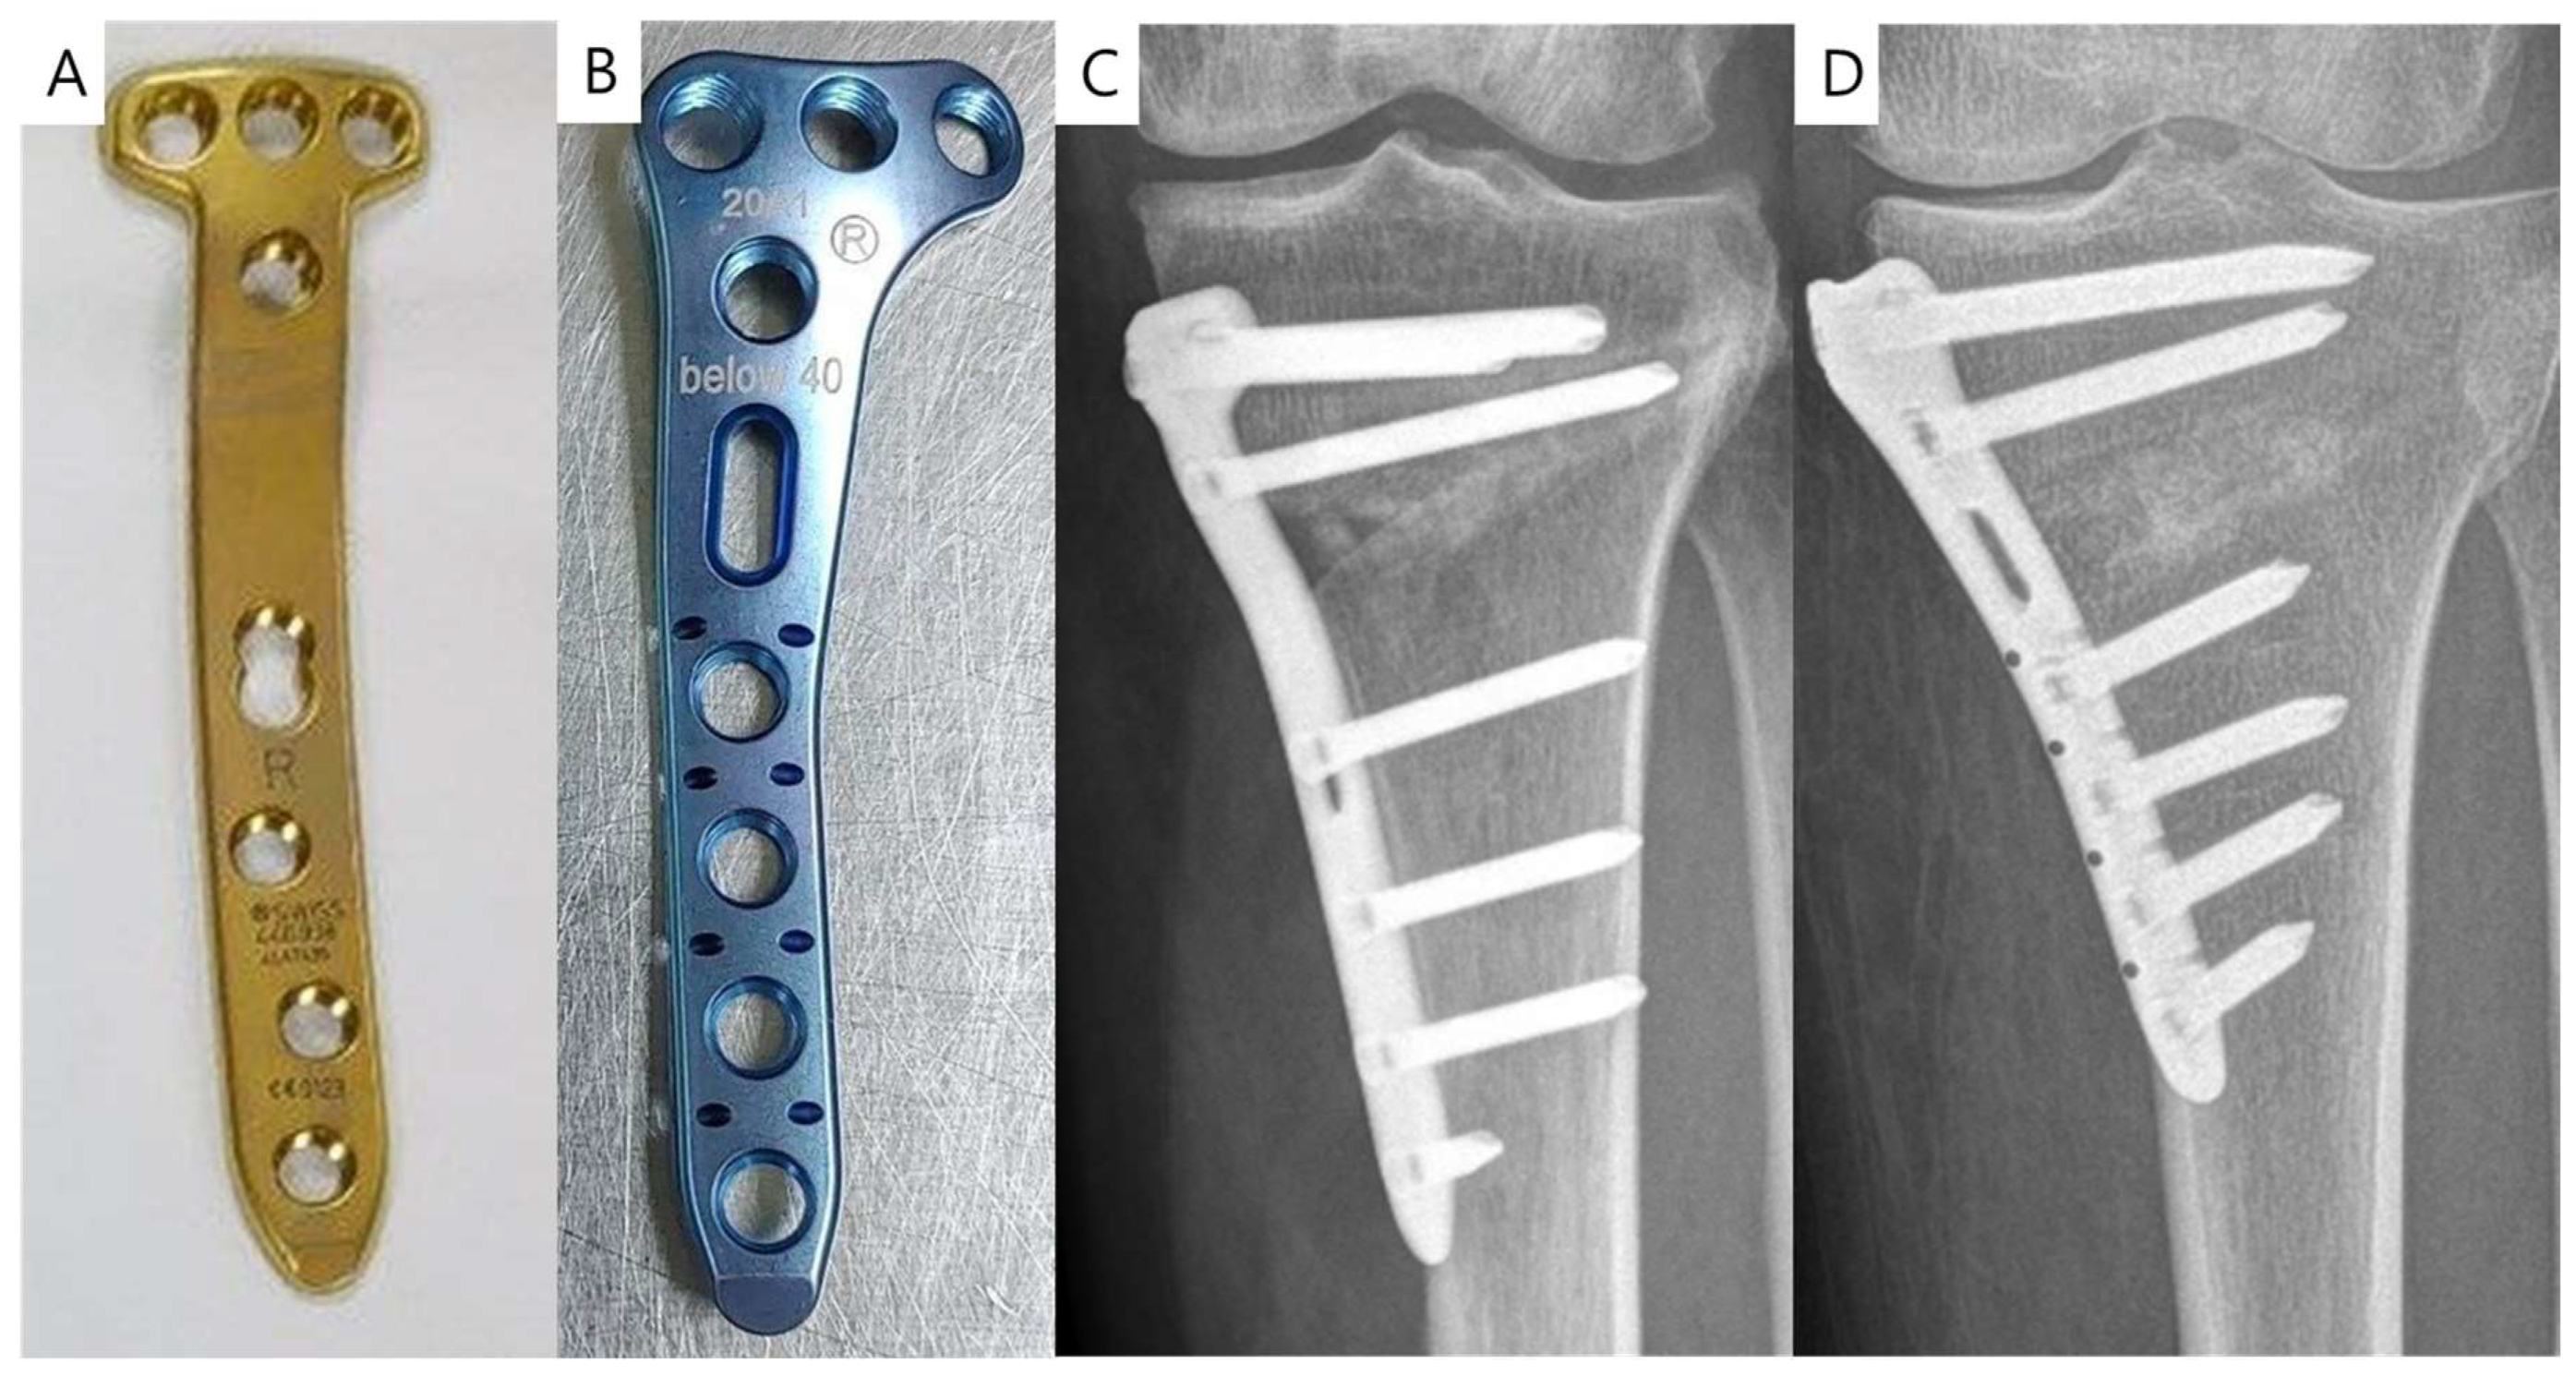

2.2. Comparison of CA Plate and IA Plate

3.2. Comparison of CA Plate and IA Plate